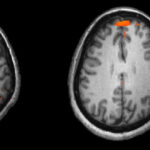

قد يكون من المعروف بأن السكريات تقوم الإضرار بمينا الأسنان، ولكن ما هو أكثر ترويعاً هو أن هذا السكر يمكن أن يضر بقوة العقل أيضاً، حيث بينت البحوث أن تناول الكثير من السكر يمكن أن يسبب ضعف وظيفة الإدراك ويقلل من البروتينات التي تعتبر ضرورية للذاكرة والقدرة على الاستجابة، كما أظهرت إحدى الدراسات التي تم إجراؤها على الفئران التي كانت تتغذى على السكر أنها أصبحت أبطأ وأظهرت قلة نشاط في المشابك الدماغية عند مقارنتها مع الفئران في المجموعة الضابطة، كما أنه وبحسب (لونغ غيليسبي) فإن تناول كميات كبيرة من السكر يرتبط بالإصابة بمتلازمة الأيض، وهي مجموعة من الحالات المترابطة التي لا تشتمل فقط على تراجع الوظائف الإدراكية، ولكن ربما على أحداث تغييرات في البنية الدماغية أيضاً.

- التقليل من السكريات المضافة يقلل من احتمال الإصابة بمرض الزهايمر والخرف

إن النظام الغذائي الغني بالسكر المضاف يقلل من إنتاج مادة كيميائية تعرف باسم عامل التغذية العصبية المستمد من الدماغ (BDNF)، والتي تساعد الدماغ على تشكيل الذكريات الجديدة وتذكر الذكريات القديمة، ولكن عادة ما تكون مستويات الـ(BDNF) منخفضة بشكل خاص لدى الأشخاص الذين لديهم ضعف في أيض الجلوكوز (مرضى السكري ومرضى ما قبل السكري) وهذا الانخفاض في مستويات (BDNF) يرتبط بالإصابة بالعته ومرض الزهايمر.